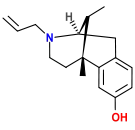

Morphinans

Morphinan series

- 3-Hydroxymorphinan

- 4-Chlorophenylpyridomorphinan

- Cyclorphan

- Levargorphan

- Levorphanol

- Levophenacylmorphan

- Levomethorphan

- Methorphan (racemethorphan)

- Morphanol (racemorphanol)

- Norlevorphanol

- N-Methylmorphinan

- Oxilorphan

- Phenomorphan

- Proxorphan

- Ro4-1539

- Stephodeline Xorphanol

Structures

| Other morphinans | ||||

|---|---|---|---|---|

4-chlorophenylpyridomorphinan 4-chlorophenylpyridomorphinan |

Cyclorphan Cyclorphan |

Dextrallorphan Dextrallorphan |

Levargorphan Levargorphan |

Levophenacylmorphan Levophenacylmorphan |

Levomethorphan Levomethorphan |

Norlevorphanol Norlevorphanol |

N-Methylmorphinan N-Methylmorphinan |

Oxilorphan Oxilorphan |

Phenomorphan Phenomorphan |

Dextromethorphan Dextromethorphan  levomethorphan levomethorphan |

Morphanol Morphanol |

Ro4-1539 Ro4-1539 |

Stephodeline Stephodeline |

Xorphanol Xorphanol |